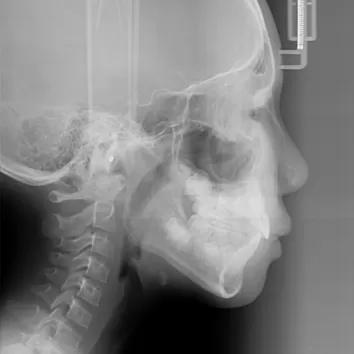

X-rays before treatment

[Panoramic Radiography/Lateral Cephalogram]